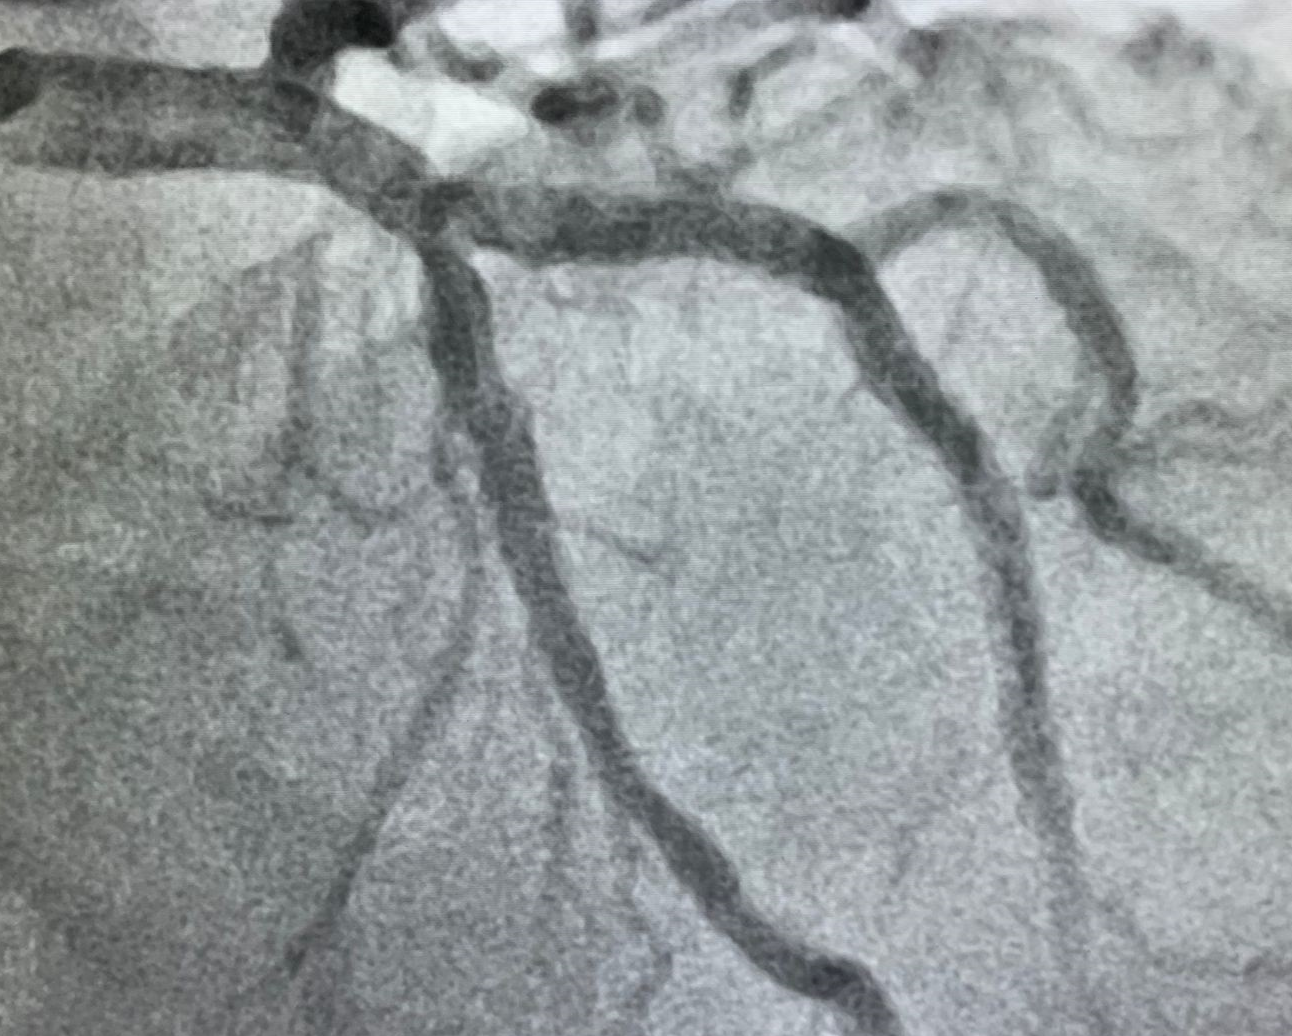

O Hospital Moriah acaba de entrar em um novo nível na cardiologia intervencionista. Essa semana realizamos um procedimento, trazido para o Brasil há 4 meses, para desobstrução de artérias com lesões severas e muito calcificadas que impedem a realização da angioplastia arterial (tratamento minimamente invasivo das artérias entupidas, que podem levar ao infarto, entre outras complicações).

A angioplastia arterial é um tratamento já bastante disseminado para esses casos, onde se coloca dentro da artéria entupida um artefato, semelhante a uma mola, chamado de stent, que abre novamente a artéria para a passagem do sangue. Mais recentemente, passamos a usar os stents farmacológicos, ou seja, que liberam progressivamente medicações para tratar as paredes da artéria e evitar nova calcificação.

O Shockwave é um equipamento de litotripsia intravascular (um pequeno cateter que segue por dentro da artéria até a lesão), que emite ondas de choque que quebram o cálcio acumulado e que está obstruindo a artéria.

Dessa maneira, a equipe médica pode entrar com o stent que será implantado e passará a liberar a medicação que vai evitar novas obstruções.

Artérias muito comprometidas não conseguem receber o stent, limitando as opções de tratamento do paciente.

O uso do Shockwave não altera a recuperação do paciente e nem o tempo de internação. O primeiro caso operado no Hospital Moriah foi coordenado pelos Drs. Leonardo Seli Llorente Aguilera e Gabriel Dodo e o paciente já teve alta e passa bem.